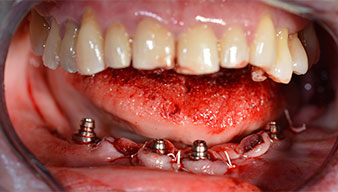

Angled abutments (35°) were screwed in to compensate for the divergence of the distal implants, with the result that the emergence profile of all implants was as perpendicular as possible to the bite plane. This is a prerequisite for occlusal placement of the provisional and subsequently the permanent denture (Fig. 15 and 16).

The impression and bite registration were then performed so that the dental technician could begin producing the provisional restoration immediately. This was then screwed in on the same day (Fig. 17 and 18).

Following the time required for the osseointegration, the final impression of the implants could be performed and the final denture produced accordingly (Fig. 19 and 20). At this point, the dentist and patient were able to decide together whether to use a ceramic or acrylic veneer and a zirconium or metal framework. In this case, Dr. Pascu’s team decided on an acrylic veneer based on the unclear prognosis for the maxillary dentition and the fact that tooth 24 is elongated. This type of veneer is generally considerably easier to adapt and can thus be subsequently altered to reflect the new situation in the maxilla.